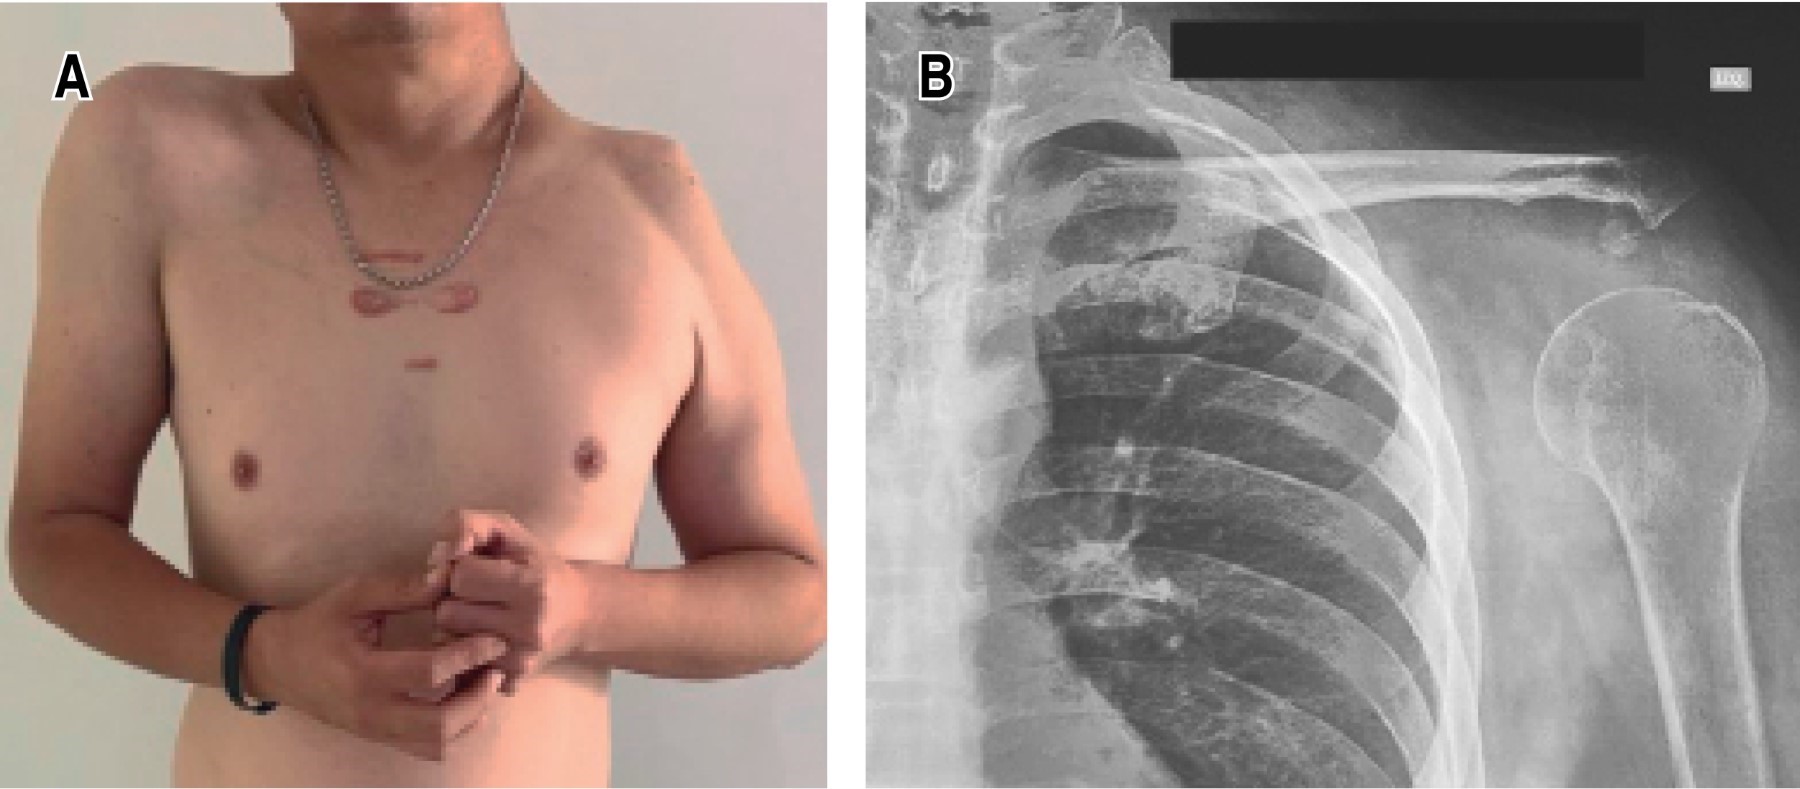

Debido al tamaño de la tumoración, su localización, así como el compromiso funcional de las estructuras anatómicas, aunado al deseo del paciente, se decidió un manejo quirúrgico. Se optó por una escapulectomía total intraarticular izquierda (Figura 3), siendo una resección tipo III A de Malawer, con suspensión humeral más la reinserción del redondo menor, deltoides e infraespinoso a la porción distal de la clavícula. El acto quirúrgico se llevó a cabo sin complicaciones. Se envió una biopsia de la tumoración para su estudio histopatológico, el cual reportó que se trataba de una neoplasia mesenquimática maligna de estirpe cartilaginosa con arreglo pseudonodular separada por áreas hialinizadas por matriz basófila con alta celularidad constituida por condrocitos que formaban lóbulos mal definidos, observándose mitosis aisladas; junto con la infiltración a trabéculas óseas, el sistema músculo esquelético y tejido fibroadiposo; además de la ausencia de invasión linfovascular, perineural y piel. Se concluye el diagnóstico final de un condrosarcoma central grado 2 OMS 2020.

Posterior al manejo quirúrgico, el paciente fue canalizado a rehabilitación y al servicio de oncología, sin embargo, el paciente decidió no acudir a dicho servicio por razones personales. A diez meses del evento quirúrgico, se dio seguimiento a través de la evaluación funcional del paciente (Figura 4). En cuanto a la discapacidad del brazo, hombro y mano, usando la escala DASH (Disabilities of the Arm, Hand and Shoulder), el paciente obtuvo una calificación de 45 puntos, lo cual representa que desde su perspectiva puede usar funcionalmente el miembro superior. Durante la evaluación presentó una estabilidad satisfactoria, pero con una movilidad con funciones deficientes, acorde los 65 puntos obtenidos con la escala de Rowe (estabilidad: 50 puntos, movimiento: 5 puntos, función: 10 puntos). Para evaluar las mejoras funcionales después del procedimiento quirúrgico del hombro, se aplicó el Simple Shoulder Test, que reportó un resultado de 41 puntos, debido a la limitación para abducción, rotación interna y flexo-extensión del hombro izquierdo. Cabe mencionar que el paciente se refirió independiente para su actividad laboral, así como vida diaria, gracias la movilidad completa del codo, muñeca y mano. Actualmente, el paciente continúa en rehabilitación física con el fin de mejorar aún más la funcionalidad del miembro superior izquierdo.